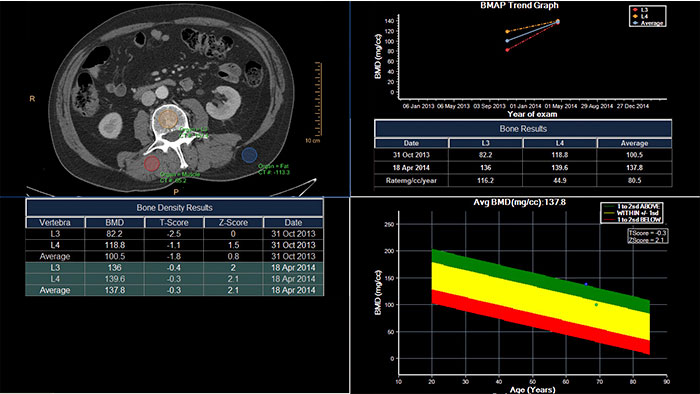

CT Bone Mineral Analysis (BMA) is designed to measure bone density in one or multiple time points. Using an internal reference method*, the application reduces reproducibility errors in multiple time point measurements and provides T- and Z- scores which help physicians assess the risk of osteoporosis.

*Muller DK, et al., Phantom-less QCT BMD system as screening tool for osteoporosis without additional radiation. Eur J Radiol. 2011; 79(3):375–81.